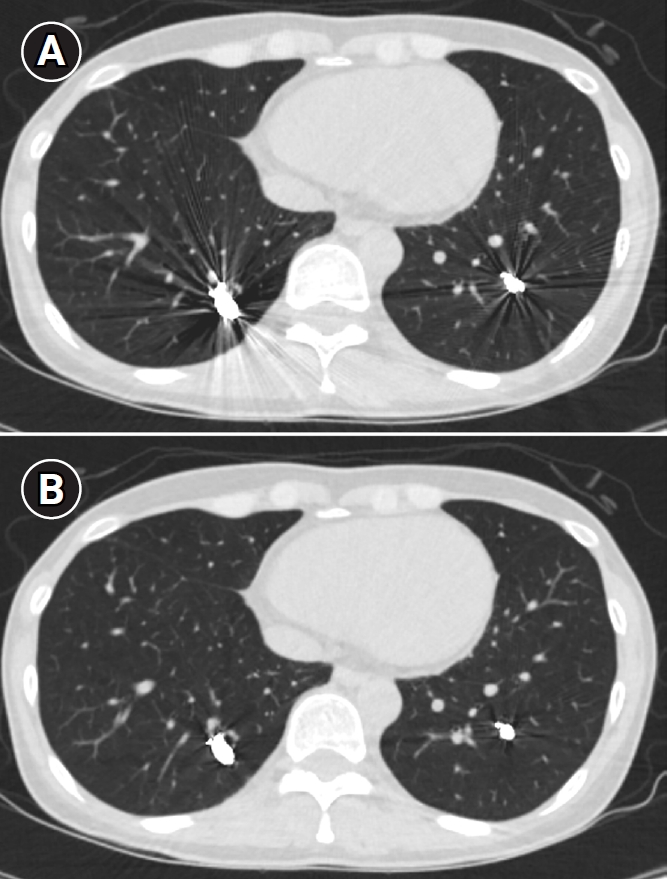

Fig. 5.

Embolization procedure in a patient with a feeding artery diameter of 2.6 mm and a venous sac diameter of 8 mm in the right lower lobe. (A) Selective angiography of the right lower lobe pulmonary arteriovenous malformation. (B) A 7 mm Amplatzer vascular plug type IV (arrow) was deployed into an approximately 8 mm venous sac, and it was determined that this would not provide adequate embolization effect. (C) By repositioning the Amplatzer plug and deploying it at the distal part of the feeding artery (arrow), it becomes clear that an Amplatzer vascular plug sufficiently larger than the feeding artery’s size is needed to effectively achieve embolization.

Fig. 5. Embolization procedure in a patient with a feeding artery diameter of 2.6 mm and a venous sac diameter of 8 mm in the right lower lobe. (A) Selective angiography of the right lower lobe pulmonary arteriovenous malformation. (B) A 7 mm Amplatzer vascular plug type IV (arrow) was deployed into an approximately 8 mm venous sac, and it was determined that this would not provide adequate embolization effect. (C) By repositioning the Amplatzer plug and deploying it at the distal part of the feeding artery (arrow), it becomes clear that an Amplatzer vascular plug sufficiently larger than the feeding artery’s size is needed to effectively achieve embolization.

Historically, detachable balloons were used as an embolization material; however, they are no longer utilized in current practice [18]. In the context of PAVM embolization, the use of coils, vascular plugs, or a combination of both is now standard practice [19-21]. Since the development of detachable coils, they have offered advantages over pushable coils, particularly in terms of repositioning during the procedure. They can even be fully retrieved and redeployed if necessary, enhancing procedural safety and control. It is crucial to prioritize minimizing the recanalization rate while ensuring the overall safety of the procedure when selecting the appropriate embolic materials and techniques. Feeding artery coil embolization was historically regarded as the standard approach, whereas venous sac embolization was discouraged because of the perceived risk of rupture [22]. However, with the introduction of newer venous sac embolization techniques, recent findings now indicate that tightly packing the venous sac with coils can achieve a higher success rate than the traditional feeding artery approach (Fig. 2) [22-25]. Additionally, vascular plugs, including micro-vascular plugs (Medtronic, Minneapolis, MN, USA) and Amplatzer vascular plugs (Abbott Vascular, Saint Paul, MN, USA) have also demonstrated a higher success rate compared to feeding artery coil embolization (Fig. 4) [26-28]. In the case of vascular plugs, the risk of device migration is relatively low. Moreover, an additional advantage is that the device can be repositioned if the sizing is not ideal or if it is not deployed in the exact desired location. This flexibility enhances the precision of the procedure (Fig. 5). In a recent European guideline, there is also a recommendation to consider vascular plug embolization as a first-line option whenever possible, rather than coil embolization [11]. Additionally, a recent meta-analysis recommended vascular plugs or venous sac coil embolization, noting that vascular plugs had a recanalization rate of 13.6% compared to 32.7% for coil-only embolization. Similarly, venous sac embolization showed a 3.8% recanalization rate, while feeding artery embolization had a rate of 24.3%. Additionally, a recent meta-analysis has recommended the use of vascular plug or venous sac coil embolization, as these techniques have demonstrated a lower persistence rate compared to other methods [21]. This shift is largely in response to the relatively high recanalization rate associated with feeding coil embolization. In the case of embolization using vascular plugs, the plug should be deployed at the most distal segment of the feeding artery just before the venous sac in order to preserve the normal pulmonary artery. Since the pulmonary artery contains less elastin and has a thinner wall compared to systemic arteries, it is more distensible [29]. Therefore, in the author's experience, oversizing by about 50% to 100% has been effective in reducing the recanalization rate. When performing venous sac coil embolization, it is important to use coils large enough to create a stable framing coil larger than the draining vein diameter, thereby preventing coil migration. After establishing this frame, the venous sac and the proximal feeding artery should be carefully packed to achieve complete occlusion.